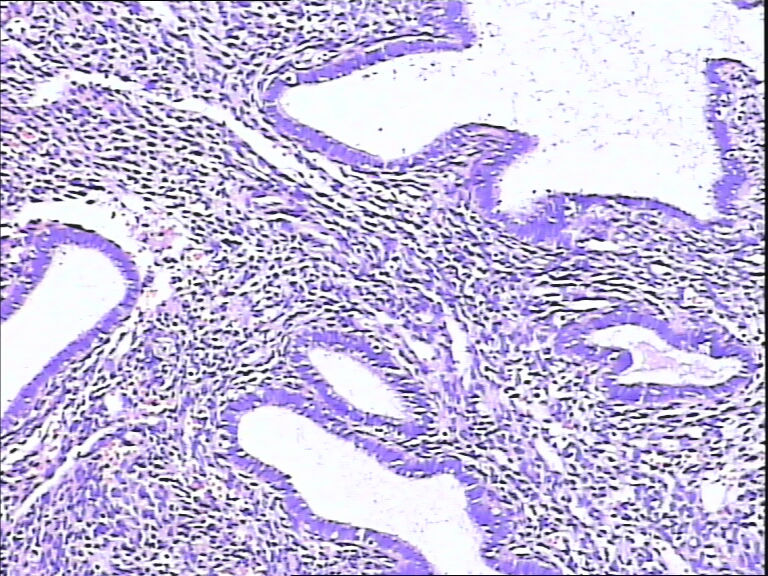

41岁,停经5年再出血。

• 宫内膜图2

图2

腺体增生,部分腺上皮有分泌。

流血期子宫内膜,腺体反应不同步。

片子不是很清楚,像是月经期子宫内膜

是不是采图有问题,片子上细胞变形严重,从轮廓看问题不大,至少不是恶性,再传点图

腺体反应不同步,部分增生期改变,部分上皮细胞有核下空泡呈早分泌期改变,是用过药物?

流血期子宫内膜,腺体反应不同步